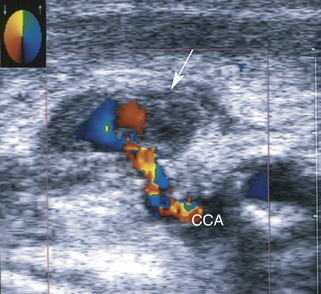

РИСУНОК 10-1. Окклюзия общей сонной артерии. На цветном допплеровском изображении видно отсутствие кровотока в общей сонной артерии ( стрелка ). Кровоток определяется во внутренней сонной артерии, которая кровоснабжается из наружной сонной артерии.

РИСУНОК 10-7. Псевдоаневризма сонной артерии. Цветовое исследование потока показывает псевдоаневризму ( стрелка ), соединенную с общей сонной артерией (ОСА) тонкой перемычкой.